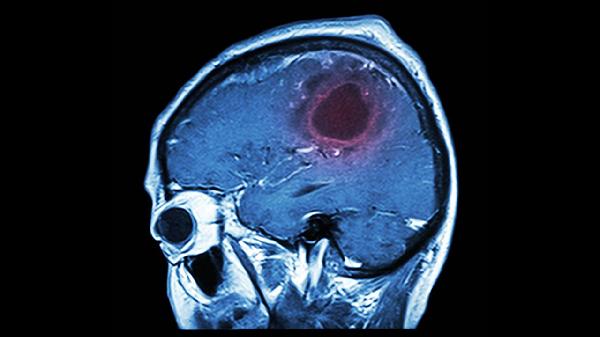

脑溢血有5个前兆信号,有1个都不能疏忽大意,要第一时间去治疗

正在刷手机的你,突然感觉太阳穴突突直跳?别急着怪罪屏幕蓝光,这可能是身体在拉预警。脑溢血这个"沉默刺客"最爱搞突然袭.击,但作案前总会留下蛛丝马迹。